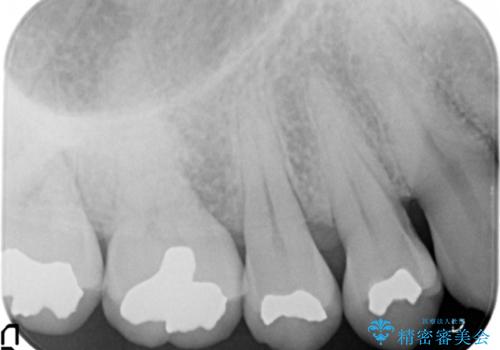

- 銀歯で詰めたところが引っ掛かるようになり舌で触ると気になる、再治療を希望され来院されました。

銀歯の劣化が見られたので化学的に安定し、長期的な予後の見込めるゴールドインレーを用いて再修復することとしました。

ゴールドは色調こそ目立ちますがあまり見えない場所には耐久性に優れ安定した修復材料です。